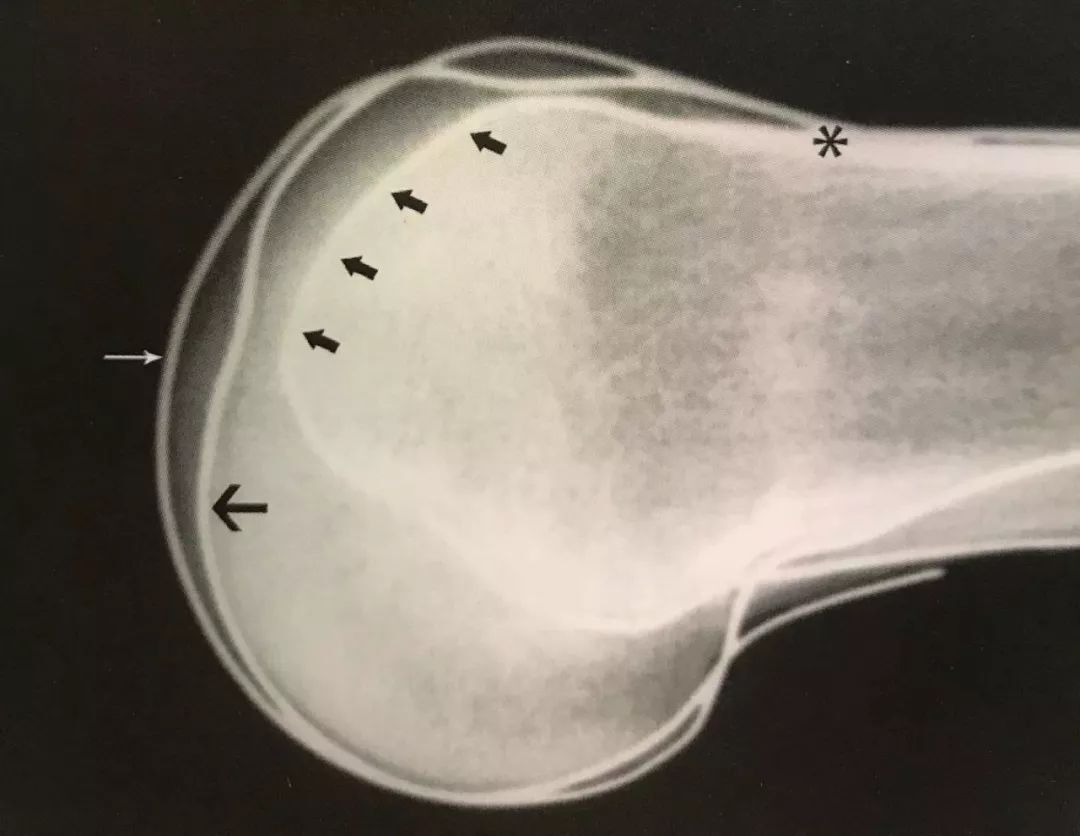

骨科技巧教你如何快速准确判断x线片下髌骨位置

髌骨高度及髌骨滑车的影像学评估 | 骨科在线